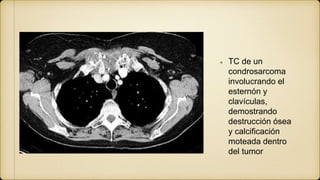

TC de un

condrosarcoma

involucrando el

esternón y

clavículas,

demostrando

destrucción ósea

y calcificación

moteada dentro

del tumor

TC de un condrosarcoma involucrandoel esternón y clavículas, demostrando destrucción ósea y calcificación moteada dentro del tumor